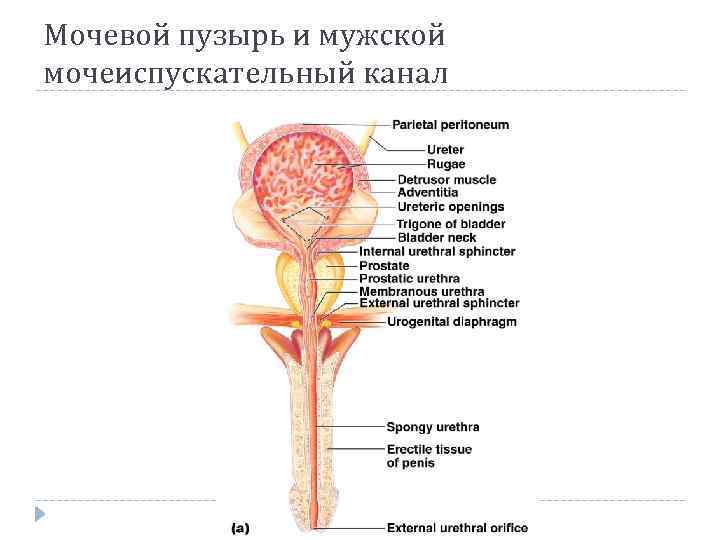

Мочевой пузырь Стенка: Слизистая Мышечная (мышца изгоняющая мочу) Адвентиция

Мочевой пузырь Стенка: Слизистая Мышечная (мышца изгоняющая мочу) Адвентиция

Мужской мочеиспускательный канал Части: предстательная, перепончатая, губчатая Сфинктеры: внутренний (гладкомышечный), наружный (произвольный) В мочеиспускательный канал открываются: протоки предстательной железы, бульбоуретральные железы, семевыбрасывающий проток

Мужской мочеиспускательный канал Части: предстательная, перепончатая, губчатая Сфинктеры: внутренний (гладкомышечный), наружный (произвольный) В мочеиспускательный канал открываются: протоки предстательной железы, бульбоуретральные железы, семевыбрасывающий проток

Мочевой пузырь и мужской мочеиспускательный канал

Мочевой пузырь и мужской мочеиспускательный канал